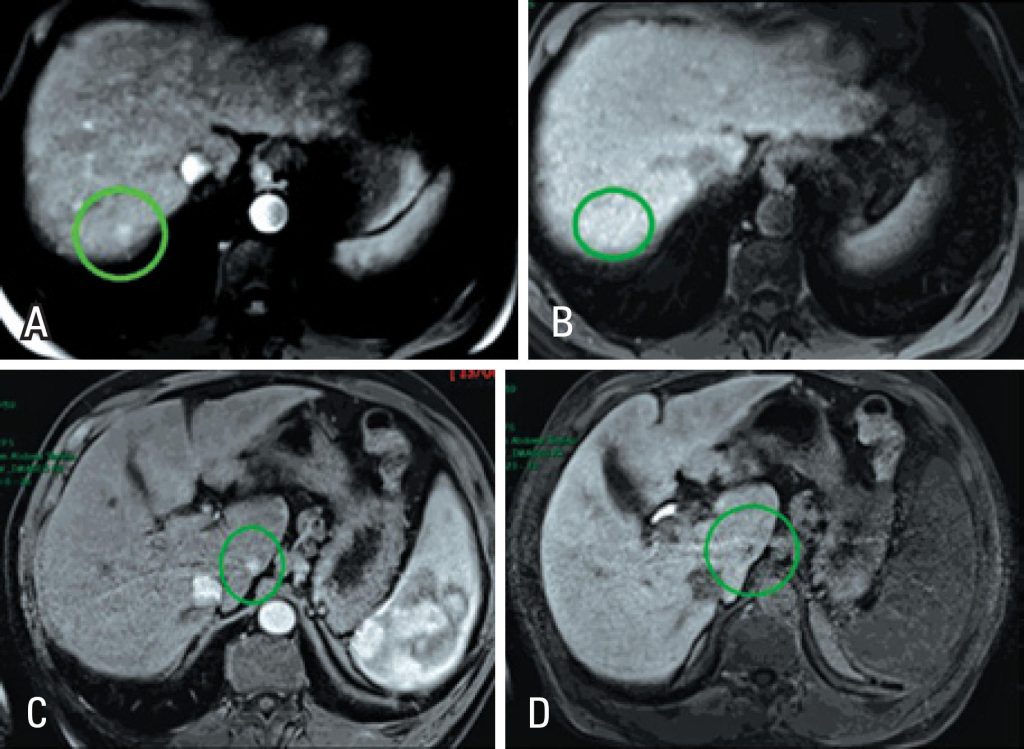

O contraste hepato-específico (ácido gadoxético – Primovist®) tem como utilidade principal melhorar a detecção e a caracterização de lesões hepáticas focais, por exemplo, em hepatopatas crônicos com suspeita de hepatocarcinoma. Por apresentar captação seletiva por hepatócitos funcionantes na fase hepatobiliar tardia, auxilia na detecção de hepatocarcinomas típicos – a maioria dos quais apresentando hipossinal nessa fase. Essa característica de imagem também auxilia na diferenciação entre nódulos regenerativos/ displásicos e hepatocarcinomas precoces (com mais de 90% de acurácia), e entre hepatocarcinomas hipervascularizados e focos de pseudorrealce arterial. Perspectivas futuras promissoras incluem sua utilização na quantificação de função e de fibrose hepáticas.